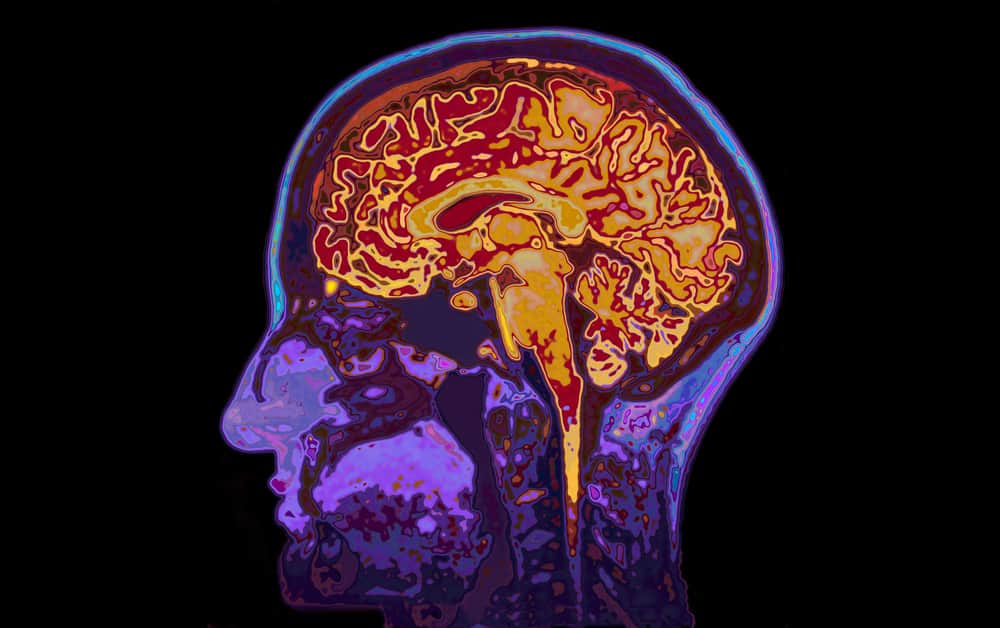

ब्रेन स्कैन से डिप्रेशन का निदान किया जा सकता है जिससे डॉक्टरों को उपचार करने में मदद मिल सकती है। जिस तरह एक इलेक्ट्रोकार्डियोग्राम (ईसीजी) हार्ट के फंक्शन को दिखाता है, उसी प्रकार फंक्शनल एमआरआई मस्तिष्क की गतिविधियों को दर्शाता है। ब्रेन स्कैन का उपयोग मस्तिष्क की बीमारियों का सही तरीके से इलाज करने के लिए किया जाता है। इसके अलावा सिर के एमआरआई के जरिए मरीज की सही बीमारी की पुष्टि की जाती है। MRI का पूरा नाम मैग्नेटिक रेजोनेंस इमेजिंग (Magnetic resonance imaging ) है। एमआरआई कई तरह की बीमारियों के निदान के लिए सबसे सुरक्षित और सटीक इमेजिंग परीक्षणों में से एक है।

किसी भी तरह के मानसिक आघात या सिर में चोट लगने पर एमआरआई कराने की आवश्यकता पड़ती है। इसकी सहायता से दिमाग में आई सूजन, ब्लीडिंग, मस्तिष्क की धमनी में समस्या (brain aneurysms) आदि असामान्यताओं का निदान किया जाता है। साथ ही चोट लगने के बाद मस्तिष्क की संरचना का पता लगाने और स्पाइनल कॉर्ड में हुए किसी तरह के विकार के निदान के लिए न्यूरोसर्जन एमआरआई स्कैन करते हैं। ब्रैन स्कैन की तरह ही एमआरआई स्कैन भी बीमारी का पता लगाने में सहायक है।

बायोलॉजिकल साइकेट्री: कॉग्निटिव न्यूरोसाइंस एंड न्यूरोइमेजिंग स्टडी के अध्ययन में शोधकर्ताओं ने बताया कि फंक्शनल एमआरआई (एफएमआरआई) द्वारा किसी व्यक्ति के मस्तिष्क में विशिष्ट न्यूरॉन्स की पहचान करने के लिए किया जाता है, जो डिप्रेशन की वजह से हुए बायपोलर डिसऑर्डर के लिए जिम्मेदार होता है।

ऑस्ट्रेलिया की यूनिवर्सिटी ऑफ सिडनी में वेस्टमेड इंस्टीट्यूट फॉर मेडिकल रिसर्च की एक टीम के नेतृत्व में शोधकर्ताओं ने 81 मरीजों पर एफएमआरआई (fMRI) के जरिए पता लगाया कि मरीजों में क्रोध, भय, उदासी, घृणा और खुशी के समय में अमिग्डाला (amygdala) की प्रतिक्रिया कैसी थी। जिनमें से 31 रोगी बायपोलर विकार से और 25 मेजर डिप्रेसिव डिसऑर्डर से ग्रस्त पाए गए। बाकी के 25 स्वस्थ पाए गए।

कुल मिलाकर, बायपोलर मरीजों की तुलना 25 यूनिपोलर मेजर डिप्रेसिव डिसऑर्डर के मरीजों से करने पर पाया गया कि बायपोलर पेशेंट्स में अमिग्डाला (amygdala) कम सक्रिय था। दोनों के बीच अंतर करने में ब्रेन स्कैन की यह टेक्निक 80 प्रतिशत सटीक थी।

इन निष्कर्षों से पता चलता है कि डिप्रेशन जैसी मनोदशा से जुड़ी बीमारियों के इलाज में नई उपचार पद्धतियां विकसित करने में भविष्य में मदद मिल सकती है। ब्रेन स्कैन पर यह रिसर्च अवसाद के निदान और उपचार के लिए सहायक साबित हुई है। ब्रेन स्क्रेन के बारे में अधिक जानकारी के लिए आप डॉक्टर की सलाह ले सकते हैं। ब्रेन स्कैन के बारे में जानने के बाद जानते हैं कि डिप्रेशन के संकेत क्या है। इसकी पहचान कैसे कर सकते हैं।